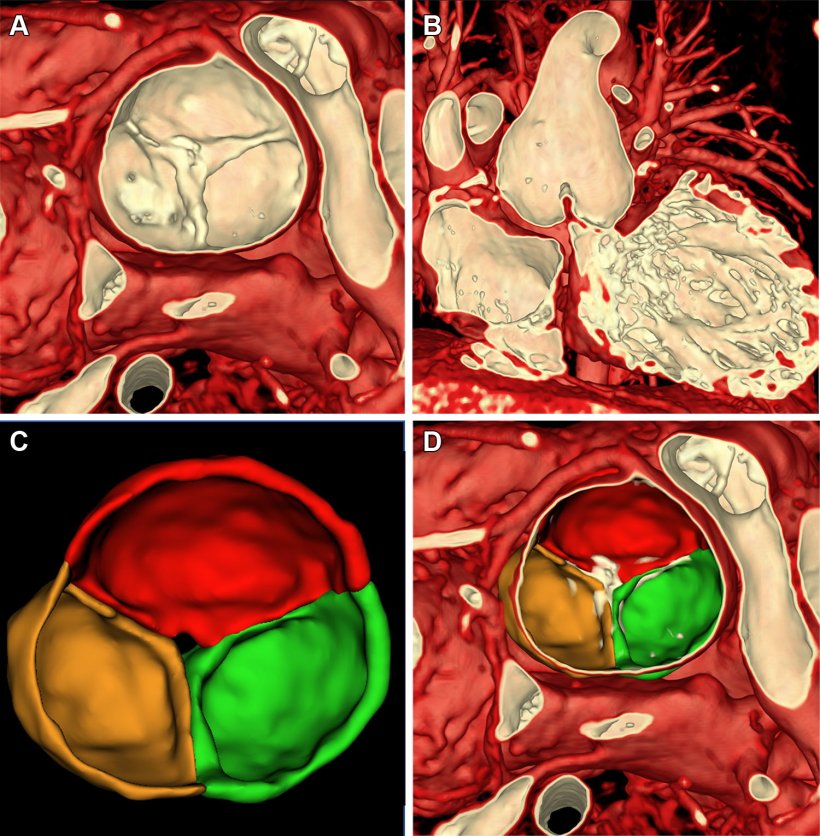

Researchers at Children’s Hospital of Philadelphia (CHOP) in Pennsylvania have developed 3D volume rendering methods for cardiac MRI that display complex structures within the heart and show how blood moves through them, much like ultrasound images but without the typical challenges of positioning angles. In their study, the researchers demonstrated how their methods guided treatment decisions in four young children who had complex congenital heart conditions.

Volume rendering is a computer graphics technique that creates 3D images directly from MRI scan data. It works by assigning colors and transparency to different tissue types based on how they appear in the MRI.

“Think of it like adjusting the settings on a photograph to highlight certain features,” said study coauthor Matthew Jolley, M.D., a pediatric cardiac anesthesiologist and cardiologist at CHOP and an associate professor at the University of Pennsylvania. “We developed specific settings that make heart muscle and heart valves visible while making blood and surrounding tissues transparent.”

The technique is particularly useful for observing blood flow through complex structures like valve leaflets—the flaps within the heart valves that are designed to open to allow blood to flow through, then close to form a tight seal and keep the blood from leaking backward in the wrong direction.

“In patients with holes in the heart structure or leaflets that don’t form a complete seal, we can now see the valve leaflets moving and identify exactly where a valve is leaking, which has not been possible with MRI before this technique,” Dr. Jolley said.

One patient in the study, a 4-year-old boy with a leaking and narrowed aortic valve, was being evaluated for valve repair or replacement surgery. The research team’s visualization tools showed the valve leaflets and a central jet of leakage, guiding the best surgical approach.